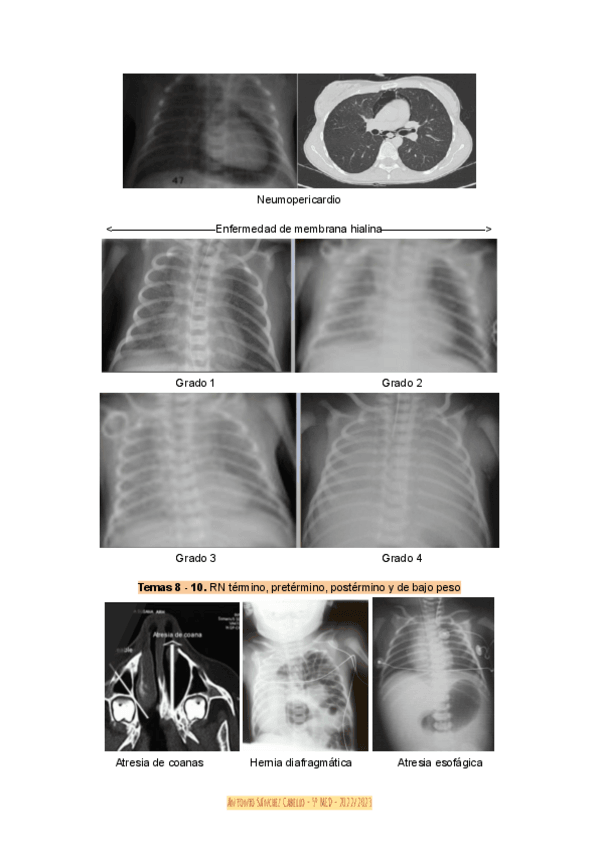

He publicado nuevos practicas de 5º PEDIATRÍA Y CIRUGÍA PEDIÁTRICA I: 2024-Seminario-Semiologia-radiologica-en-neonatologia.pdf

12 páginas